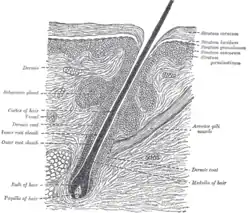

Les bactéries sont très présentes aussi sur les phanères (cheveux, poils, dessous des ongles). À partir du biofilm qui se forme naturellement sur les poils, elles peuvent pénétrer l'intérieur de la peau (et causer des problèmes inflammatoires en cas d'ongle incarné ou de poil incarné).

- Chez certaines personnes (ex. : immunodéprimées[29] ou après une chimiothérapie[29]…), ils pullulent en élargissant l'entrée des folicules pileux, en provoquant un blocage physique des follicules, ou probablement en agissant en tant que vecteurs pour les micro-organismes[30]. Ils peuvent alors favoriser la chute des cheveux et certaines affections de la peau dont l'acné rosacée[30] ; cette forme d'acné correspond toujours à des micropullulations (quadruplement en moyenne[30]) avec une densité maximale d'acariens dans les pores des joues[30] et des pullulations plus marquées dans le cas des rosacées induites par la prise de stéroïdes[30]. La prise de tétracycline par voie orale durant un mois n'induit aucun changement dans le nombre des demodex comptés sur la peau touchée par une acné rosacée[30],[31]. Le demodex se reproduit au bout de 14 jours environ, avec un métabolisme et une viabilité dépendant notamment de la température[32].